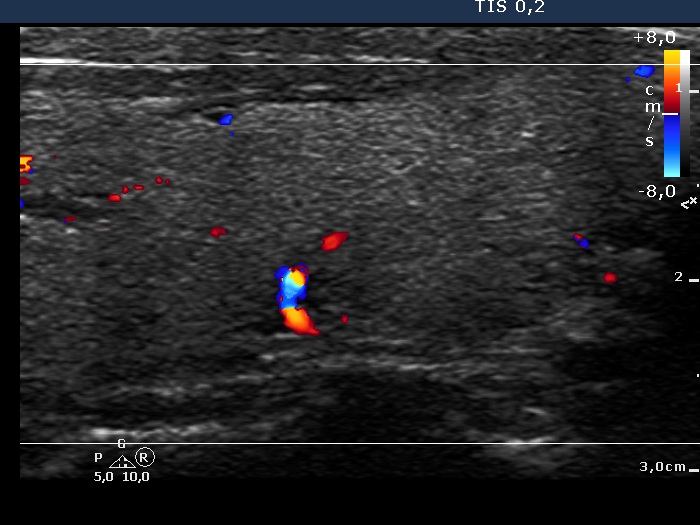

Ultrasonography. The thyroid was echonormal. There was a discrete, deeply hypoechoic area in the dorsal part of the right lobe. Although the dimensions were only 4x7x5 mm, width, depth, length, respectively, the lesion would correspond to a TIRADS 5 lesion because it was very hypoechoic and presented with irregular shape. However, color Doppler mode proved that this was indeed a vessel and not a solid thyroid tissue. The left lobe had a minimally hypoechoic lesion which largest diameter was 9 mm.

Comments. Although some vascular patterns significantly increase the risk of malignancy, none of the TIRADS include vascularity among suspicious characteristics. The reason for this is the lack of standardization and the poor sensitivity and specificity. On the other hand, we must investigate the thyroid with color Doppler mode because we never know when to gain significant advantage of the technique. This case study is one of the many examples.